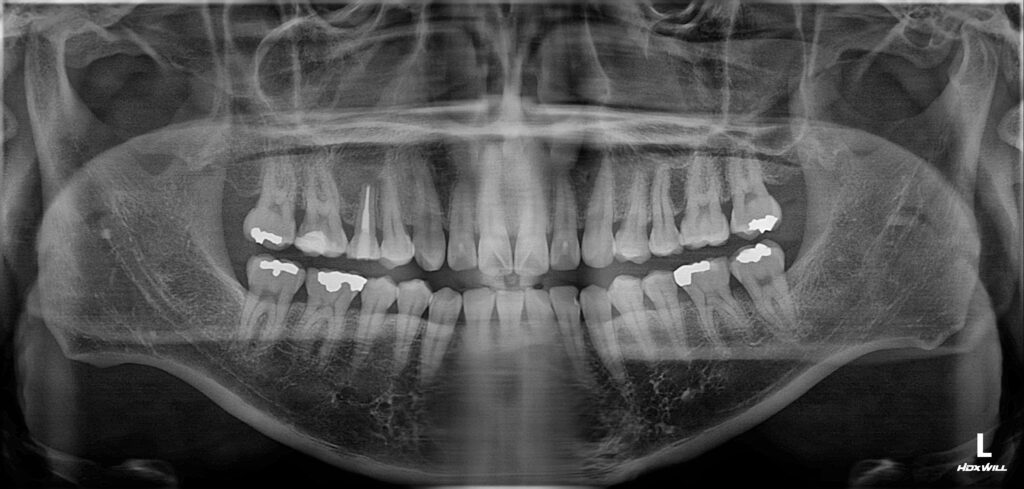

치료를 완료한 후의 모습입니다.

얼굴의 부종 감소와 눌렀을 때의

통증이 소실된 것을 확인한 뒤

최종 보철물을 시행하였습니다.

아직은 상처가 남아 있는 듯 보이는데요.